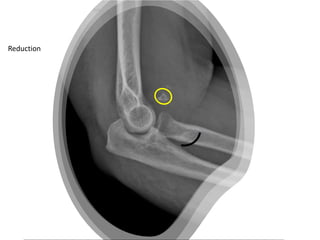

Reduction

MRI